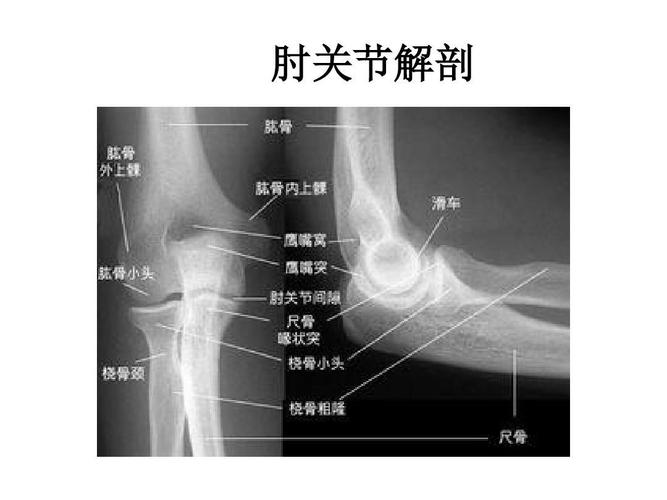

肘关节x线解剖

肘关节x线解剖及常见骨折诊断

正常肘关节x线解剖

2019--8-26 肘关节x线解剖学

肘关节解剖